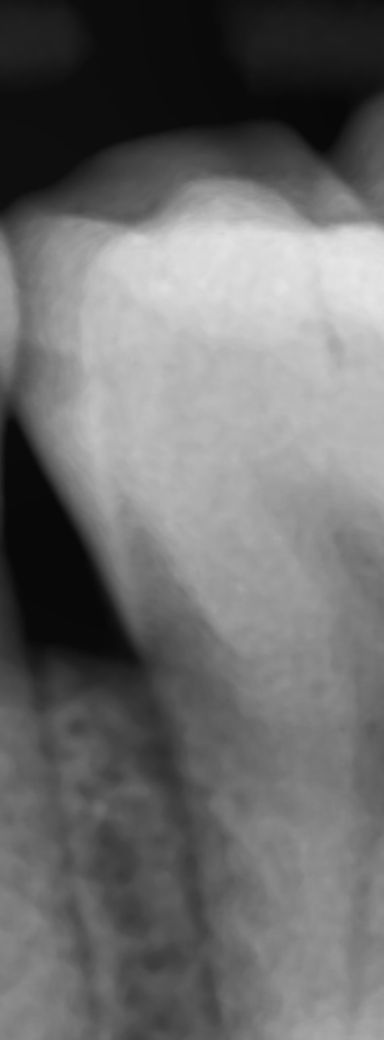

충치가 상아질 경계면 근처인가요??

충치가 상아질뚫기일보직전인가요 아니면 아직까지

상아질하고는 거리가있나요 ? 칫솔질 치실열심히하면 충분히 정지우식 될수있을까요

사진으로 봤을 경우에는 치아에 제일 바깥에 조직인 에나멜층의 충치가 생긴 것으로 보입니다.

충치의 크기는 크지 않은 것으로 보이기 때문에 치실이나 칫솔질로 꼼꼼하게 관리를 해 주는 것이 좋지만 충치의 범위는 치과에서 구간으로 확인해야 할 수 있기 때문에 치과에서 진료를 받아 보는 것이 좋습니다

치아 사이의 충치는 상아질과 매우 가깝습니다. 정지우식이 될지는 알 수 없으나 주기적으로 검진 받는 게 좋습니다.

엑스레이 상에서 저정도 충치라면 상아질까지는 충치가 진행됫을 가능성이 있습니다. 직접제거를 하면 충치는 더 사진보다 더 진행됫을꺼에요.

사이충치는 빨리 진행되는 충치입니다 상아질까지 충치가 가지는 않았으나 관리를 잘해줘야 하는 상태입니다